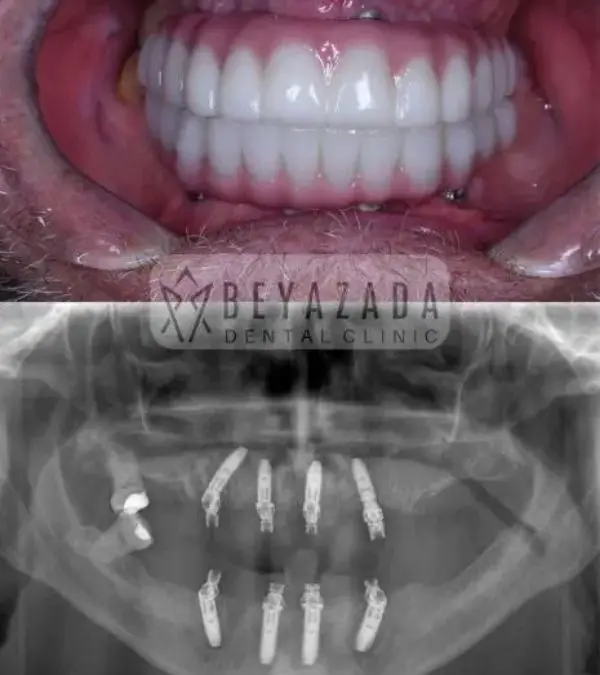

Smile Gallery

At Beyazada Dental Clinic, we take pride in the visible and emotional transformations our patients experience through All-on-Four treatment. Our case studies highlight real individuals from across Europe who arrived with serious dental challenges and left with life-changing smiles.

Before-and-after photo comparisons demonstrate dramatic improvements in facial harmony, tooth alignment, and bite functionality. These visuals showcase not only aesthetic enhancements but also restored self-esteem and quality of life.